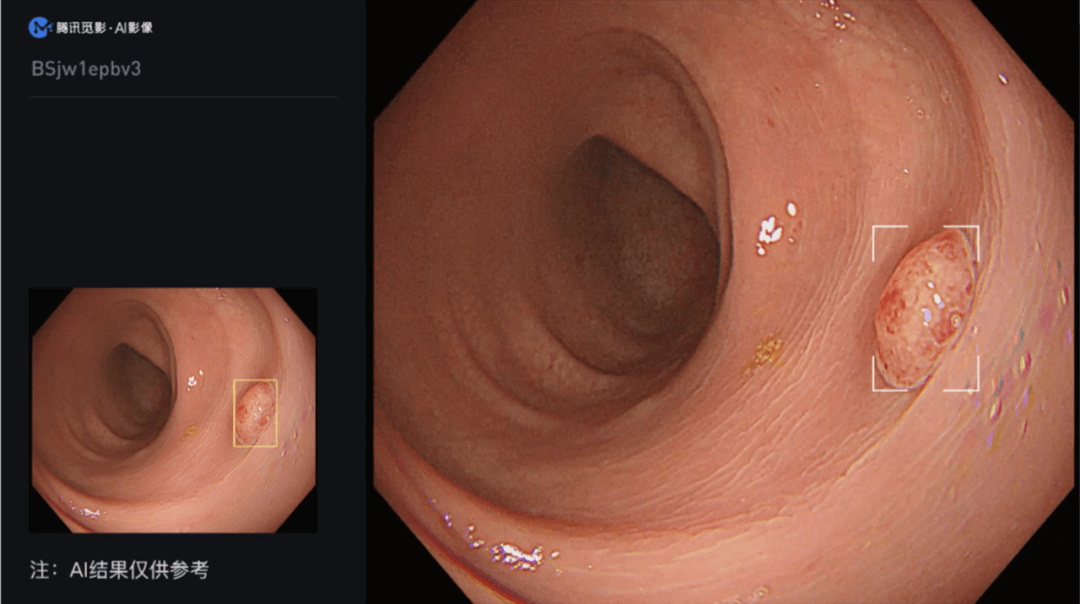

- 腾讯觅影结肠AI获批上市 助力结肠癌早发现